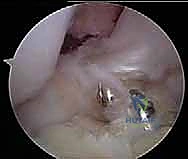

* ملاحظة هامة: يحرص الدكتور هطيف على الحفاظ على أي بقايا سليمة من الرباط الأصلي (Remnant Preservation)، حيث تحتوي هذه البقايا على مستقبلات عصبية (Proprioceptors) تساعد في تسريع التأهيل وتحسين الإحساس الحركي للركبة لاحقاً.

5. تمرير وتثبيت الحزم (Graft Passage & Fixation)

- يتم سحب حزمة (AM) عبر نفقها المخصص وتثبيتها في عظم الفخذ باستخدام أزرار تعليق معدنية صغيرة (Suspensory Fixation).

- يتم سحب حزمة (PL) عبر نفقها وتثبيتها بنفس الطريقة.

- اللحظة الحاسمة (تطبيق التوتر الديناميكي): لا يتم تثبيت الأوتار في عظم الساق عشوائياً. يقوم الدكتور هطيف بشد وتثبيت حزمة (AM) بينما الركبة مثنية بزاوية تتراوح بين 45 إلى 60 درجة. ثم يقوم بشد وتثبيت حزمة (PL) بينما الركبة في حالة تمدد شبه كامل (زاوية 10-15 درجة). هذه الخطوة العبقرية هي التي تعيد الميكانيكا الحيوية الطبيعية للركبة. يتم التثبيت النهائي في الساق باستخدام براغي تداخلية قابلة للامتصاص (Bio-absorbable Screws).